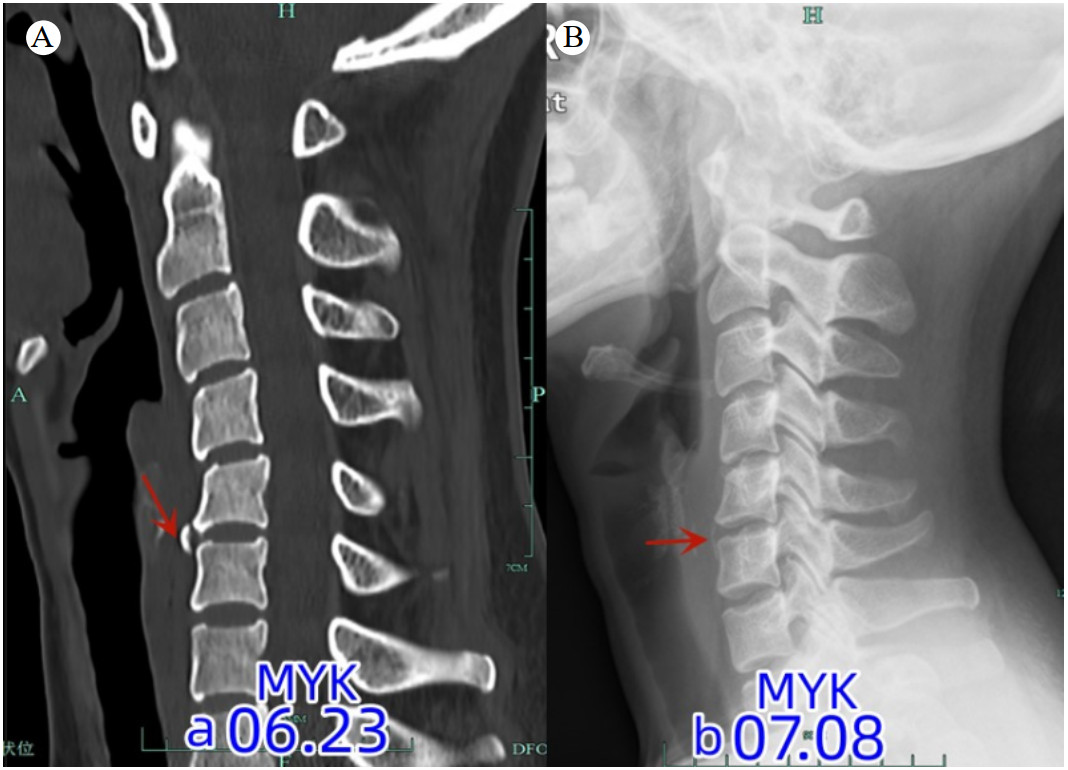

1 病例资料患者,女性,28岁,信息技术程序员,因“颈痛1 d”于6月23日到杭州市中医院就诊。患者自诉1 d前无明显诱因出现颈部疼痛,呈持续性,伴轻度咽部疼痛,无发热、咳嗽,至本院急诊就诊。患者既往有颈痛病史,影像检查见图 1。急诊给予血常规(白细胞、C-反应蛋白均正常)和颈椎CT检查(见图 2A)提示颈椎退变,曲度变直,C5/6前缘骨赘。初步诊断考虑“颈痛,颈肌扭伤”,给予洛索洛芬钠片口服治疗。6月24日患者颈部疼痛明显加剧,无法吞咽食物(吞咽困难),于五官科门诊行喉镜检查未见明显异常,于消化内科门诊就诊,考虑颈痛明显建议先于骨科就诊,未进一步行胃镜等相关检查。颈椎MRI(见图 3A)提示:颈椎椎前水肿积液,考虑“急性钙化性肌腱炎”,给予糖皮质激素(氢化泼尼松龙)、林格氏液静滴,患者自诉颈痛及吞咽困难/疼痛有所好转。6月24~26日连续静脉应用糖皮质激素3 d,患者颈部疼痛及吞咽疼痛明显缓解,改用洛索洛芬钠片继续治疗1周。7月8日于骨科门诊复查颈椎X线(图 2B)提示颈5/6前缘钙化明显缩小(较6月24日),MRI(图 3B)提示颈椎前缘水肿信号消失,颈椎退变。

| 注:A为颈椎退变,曲度变直,C5/6前缘可见增生骨赘;B为颈椎退变,曲度变直,C5/6前缘骨赘较前明显缩小 图 2 患者发病时及治疗后颈椎钙化影像学变化 |

ACTLC涉及到急诊科、骨科、神经科、五官科、消化科等学科,临床医生对此疾病认识不足及病程的良性自限性是漏诊的最主要原因。在本病例报告中,患者以“颈痛”为首发症状,初步诊断为“落枕、颈肌扭伤”,反复追问病史,患者诉“伴有咽部不适感”,在前期ACTLC的诊疗经验基础上,给予颈椎CT检查(图 2)提示颈5/6前缘钙化/骨化影,不符合典型的ACTLC,故加做MRI。病程的第2天,患者颈部疼痛明显加重,伴吞咽疼痛、吞咽困难、无法进食,MRI(6月24日)显示颈椎前缘条状水肿影,波及C3-T1节段,未出现典型的咽后壁积液,五官科喉镜检查正常。结合患者临床症状及辅助检查结果,诊断为“急性钙化性颈长肌肌腱炎(非典型部位)”,给予静脉应用糖皮质激素治疗,患者症状明显缓解,在病程的第7天,患者症状完全消失,第10天复查X线显示颈椎前缘钙化影明显缩小,MRI显示颈椎前缘水肿完全消失,验证了“钙化的自发性吸收理论”。

钙化和椎前水肿是诊断ACTLC的主要依据,钙化通常位于寰椎前弓的下方和枢椎齿状突的前方,下颈椎受累较为少见(C4/5、C5/6节段)[5-6]。除了ACTLC的典型影像征象,临床医生应熟知累及下颈椎及非钙化性肌腱炎等少见情况。Suh等[7]报道了10例ACTLC患者,9例位于C1/2节段,1例位于C5/6节段。Offiah等[8]认为无影像学钙化的患者,MRI T2加权像椎前筋膜积液对颈长肌肌腱炎具有重要的诊断意义。2012年Paik等[2]报道了9例颈长肌肌腱炎,其中3例无影像学钙化,认为无影像学钙化不能作为排除颈长肌肌腱炎的证据。此外,ACTLC需要同咽喉壁脓肿进行鉴别,ACTLC主要见于成人,儿童出现类似表现时应首先考虑咽后脓肿或咽周脓肿,多存在上呼吸道感染病史,伴有高热、吞咽疼痛,严重者可致窒息,增强MRI呈环形强化,且常伴淋巴结肿大,有助于鉴别。

钙化性肌腱炎的自然病程通常分为三期:钙化前期、钙化期、钙化后期;钙化期又分为钙化形成期、静止期和重吸收期[9]。在钙化的吸收阶段,钙化沉积物被炎性细胞吞噬,诱发炎症反应,这是患者最痛苦的阶段[9]。Tezuka等[10]回顾文献总结17例ACTLC患者钙化物影像学吸收现象,发现吸收时间分别为 < 1个月(11例)、1~2个月(4例)、> 2个月(2例);且临床症状并不完全与影像学表现相一致,临床症状的完全恢复需要1~2个月,钙化物的完全消失通常需要3~4周。本病例图 1A显示C5/6前缘未见骨化,属于钙化前期;而图 1B显示钙化,而无相应的临床症状,属于钙化期;图 2A出现典型的临床症状,属于吸收期;在末次随访时,C5/6前缘钙化影几乎完全消失,属于钙化后期。ACTLC为良性自限性疾病,疼痛多在1周达到高峰,2~4周缓解[11]。本病例经过糖皮质激素的治疗,病程持续1周即完全缓解,对ACTLC充分认识的基础上早期应用糖皮质激素能够大大缩短病程,减轻患者痛苦。